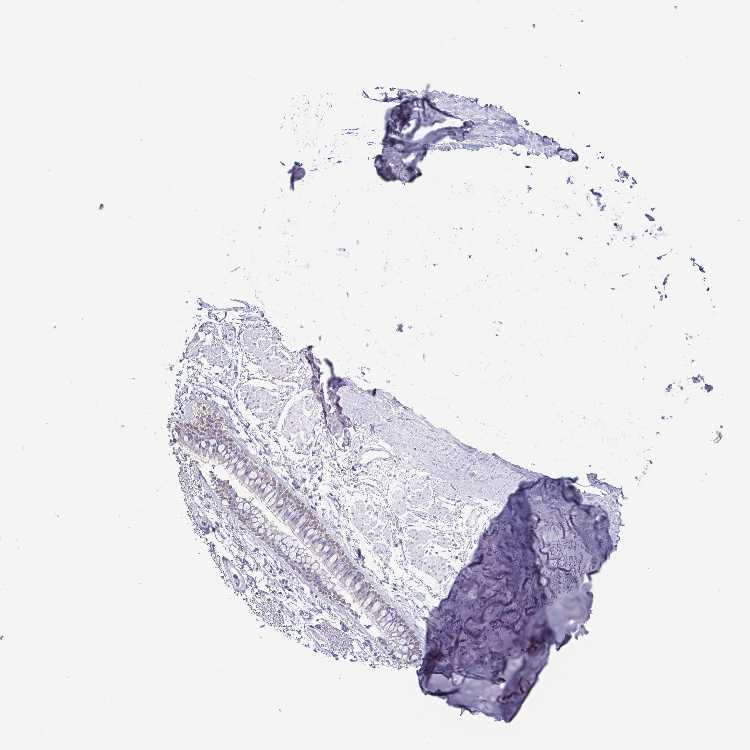

SOFT TISSUE 1 - Antibody stainingi

Antibody staining in the annotated cell types in the current human tissue is reported as not detected, low, medium, or high, based on conventional immunohistochemistry profiling in selected tissues. This score is based on the combination of the staining intensity and fraction of stained cells.

Each image is clickable and will lead to virtual microscopy that enables deeper exploration of all samples and also displays staining intensity scores, fraction scores and subcellular localization as well as patient and tissue information for each sample.

Antibody HPA012014Antibody CAB000132

Chondrocytes Not detected-

Fibroblasts Not detectedNot detected

SOFT TISSUE 2 - Antibody stainingi

Peripheral nerve Not detected-